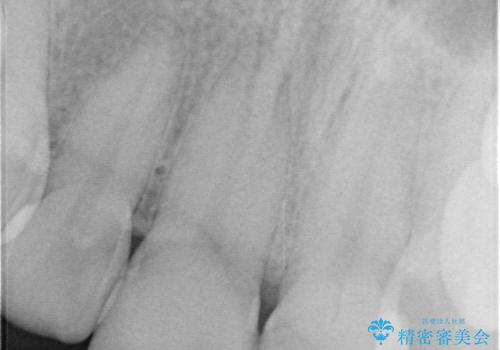

前歯の根のところに違和感がある|根尖性歯周炎|精密根管治療|オールセラミッククラウン|見た目も改善

- 前歯の違和感を主訴にご来院された患者様です。

根尖性歯周炎に罹患し根の先に膿が溜まっているのが原因でした。

精密根管治療後、オールセラミッククラウンで治療を行いました。